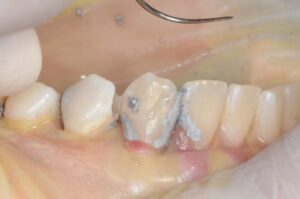

例えば、虫歯がひどく単に充填するだけでは歯の強度を元に戻すのが難しい歯の場合ピンを使います。

下の写真のようにピンを打って支えを作った歯にアマルガムを充填し、そのアマルガムを残したまま、ゴールド修復を行い、歯を被せることによって、強度を取り戻した歯にすることができます。

これらの治療は神経を刺激しない位置にチタン製でできたピンを打ち込まねばならず非常に神経を使う仕事です。